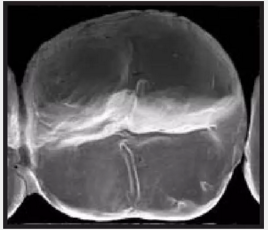

復(fù)合樹脂在即刻充填后,觀察其在電子顯微鏡下的掃描圖像,本次研究選擇了9種具有代表性的復(fù)合樹脂材料。

3.png

Esthet.X HD Dentsply 登士柏